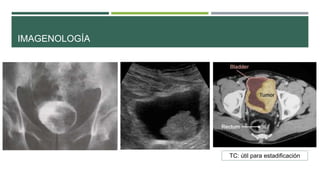

IMAGENOLOGÍA

TC: útil para estadificación